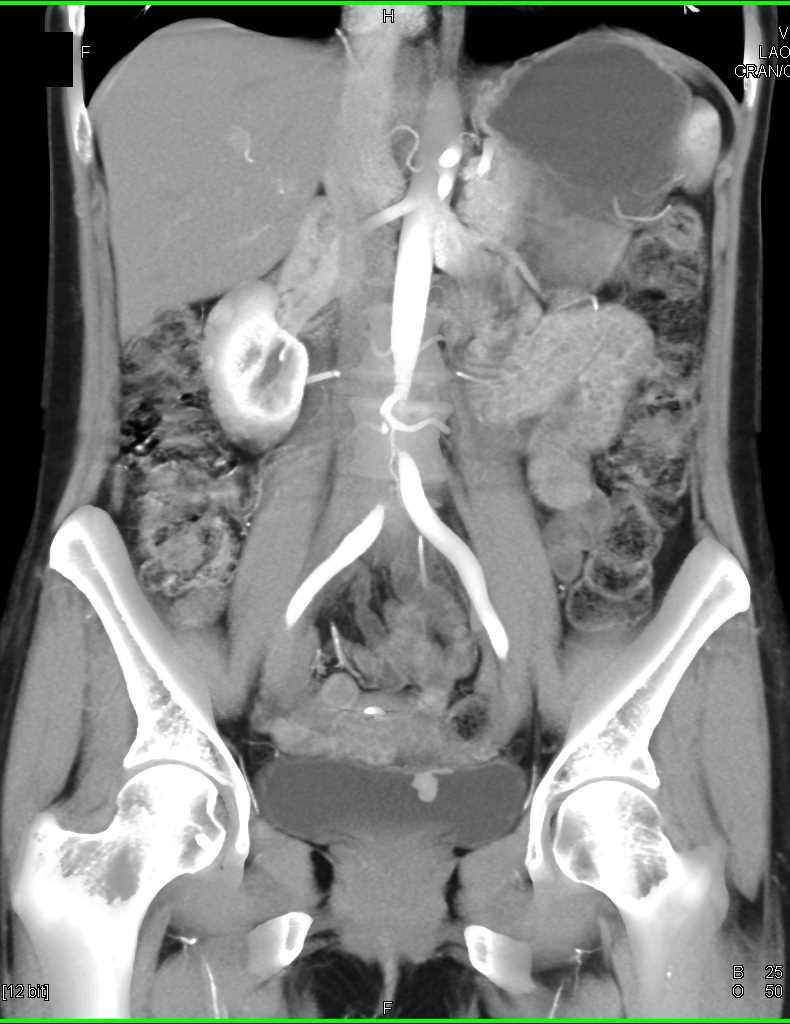

Bladder Cancer with Active Bleed